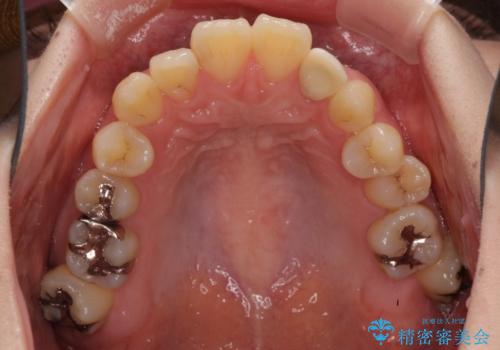

- 下顎の歯が舌側に倒れていることと、前歯の咬み合わせの不具合を気にして来院された患者様です。

受け口傾向の口元であるため、下顎左右小臼歯各1歯を抜歯して歯列を整えることとしました。

前歯には治療中の仮歯が装着されていたため、矯正治療後にオールセラミッククラウンにて補綴治療を行うこととしました。